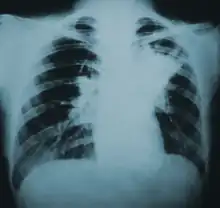

Lung infiltration in blastomycosis.

Blastomycosis manifests as a primary lung infection in about 79% of cases.[8] The onset is relatively slow and symptoms are suggestive of bacterial pneumonia, often leading to initial treatment with antibacterials. Because the symptoms are variable and nonspecific, blastomycosis is often not even considered in differential diagnosis until antibacterial treatment has failed, unless there are known risk factors or skin lesions.[8] The disease may be misdiagnosed as a carcinoma, leading in some cases to surgical removal of the affected tissue.[19] Upper lung lobes are involved somewhat more frequently than lower lobes.[20] If untreated, many cases progress over a period of months to years to become disseminated blastomycosis.

Blastomycosis in the lungs may present a variety of symptoms, or no symptoms at all.[8] If symptoms are present they may range from mild pneumonia resembling a pneumococcal infection to acute respiratory distress syndrome (ARDS).[8] Common symptoms include fever, chills, headache, coughing, difficulty breathing, chest pain, and malaise.[8] Without treatment, cases may progress to chronic pneumonia or ARDS.[8]